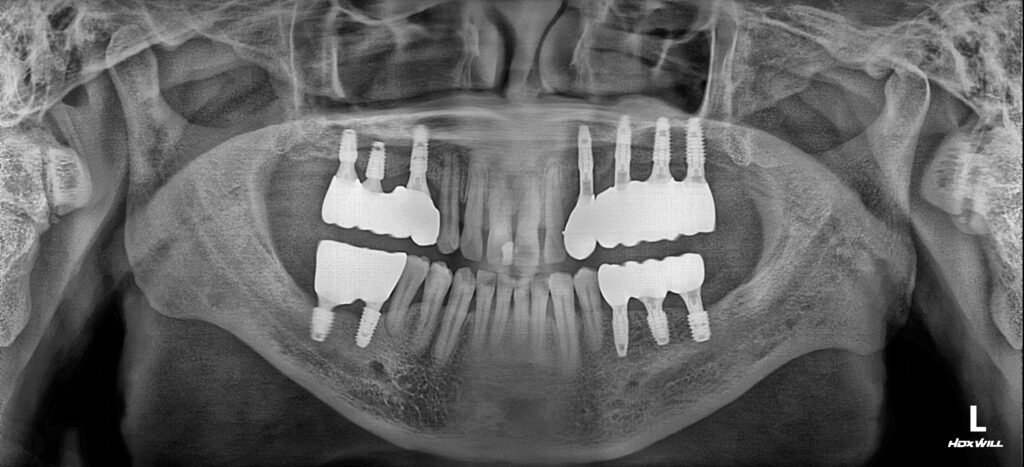

25.03.19

약 1년 4개월의 치료기간 후, 최종 보철물까지 완성된 모습입니다!

치조골의 상태를 확인하며 안정적으로 임플란트 식립이 진행된것을 볼 수 있습니다.